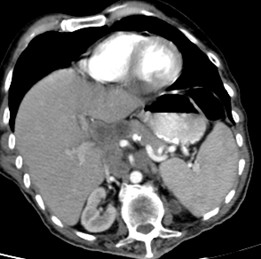

Un autre cas de cancer epidermoide du

1/3 moyen de oesophage avec metastase ganglionaire

pulmonaire . Bilan pre-therapeutique .

- Image TDM fenetre mediastinal en coupe

coronal ( frontale) et en coupe axiale a

traverse la tumeur . Image du tumeur de

oesophage avec extention locaux aortique et au

ganglions pulmonaires